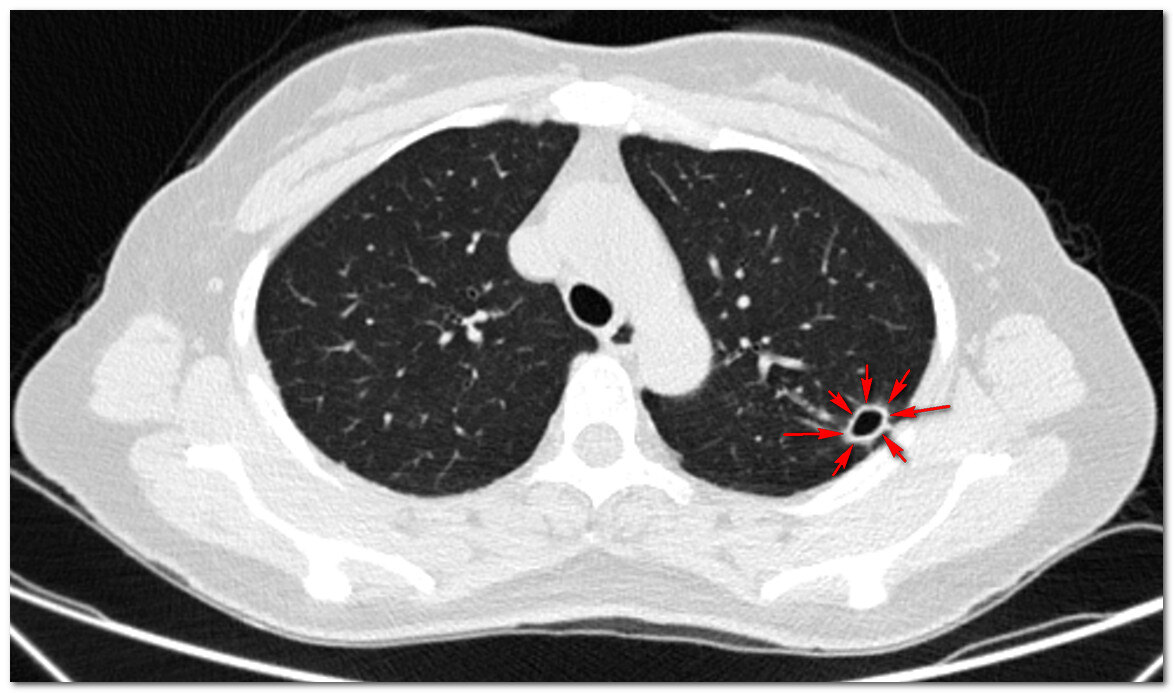

左肺空洞

这个女病人是双上肺多发的斑片 , 点状病灶 , 在左上肺形成了一个小空洞 , 其实这样的病灶在她身上已经存在了很久 , 每次感冒会发热 , 由于疫情防控需求 , 每次发热到医院都需要拍片子 , 一拍片子就查出来肺部病灶 , 就被要求在医院隔离等待核酸等检查结果 , 给生活带来了很多麻烦 。